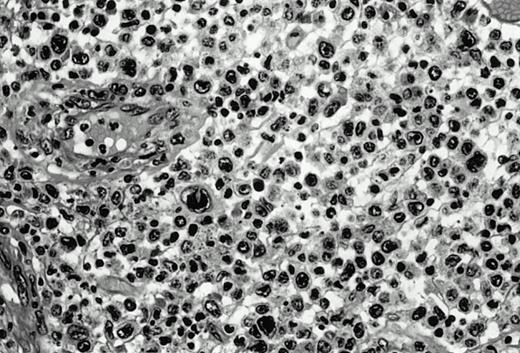

Three cases (cases no. 1 to 3) were located in the nasal cavity. The neoplastic infiltrate consisted of medium and/or large pleomorphic lymphoid cells (Fig 1)intermingled with variable numbers of small lymphoid cells, plasma cells, eosinophils, and histiocytes. Features of angiocentrism and angioinvasion, epitheliotropism, and areas of necrosis were observed in all three cases. Patient no. 4 presented with disease restricted to the lung and an open-lung biopsy was available. The neoplastic infiltrate was composed of large atypical lymphoid cells and was predominantly interstitial without extensive destruction of the normal architecture. Features of angiocentrism, angioinvasion, and epitheliotropism were present (Fig 2A and B). Case no. 5 involved the larynx, extending to the piriform sinus, the ventricle, and the arytenoid. One month later, the lymphoma disseminated to the subcutaneous tissue in the spinal region and biopsy specimens from both sites were available. The neoplastic cells were medium and large, with abundant clear cytoplasm and slightly irregular nuclei with dense chromatin. Epitheliotropism was present in the larynx mucosa. Small foci of necrosis and angiocentrism were seen without angioinvasion. Three patients presented with cutaneous disease. Cases no. 6 and 7 were comparable, as both histories started with necrotic subcutaneous nodules of the thigh, which on histologic analysis were characteristic of cytophagic histiocytic panniculitis without evidence of lymphoma (Fig 3A). Second excisional biopsies of cutaneous nodules obtained 7 and 5 months later, respectively, showed characteristic features of lymphoma in both cases (Fig 3B). However, in case no. 6, skin biopsy specimens showed an epidermotropic PML lymphoma extending to the dermis and the subcutaneous tissue, whereas in case no. 7, the neoplastic infiltrate consisted of a PSC confined to the subcutaneous tissue, admixed with benign histiocytes that showed phagocytosis. Patient no. 8 presented with recurrent skin lesions with spontaneous remission over a period of 10 years. The initial skin biopsies demonstrated an intense epidermotropic neoplastic infiltrate that extended to the superficial and deep dermis composed of atypical PML cells. All cutaneous cases displayed features of angiocentrism, but angioinvasion was observed only in case no. 6 and foci of necrosis in cases no. 6 and 8.

Pleomorphic large-cell γδ T-cell lymphoma (case no. 3) (nasal biopsy specimen with hematoxylin-eosin stain).